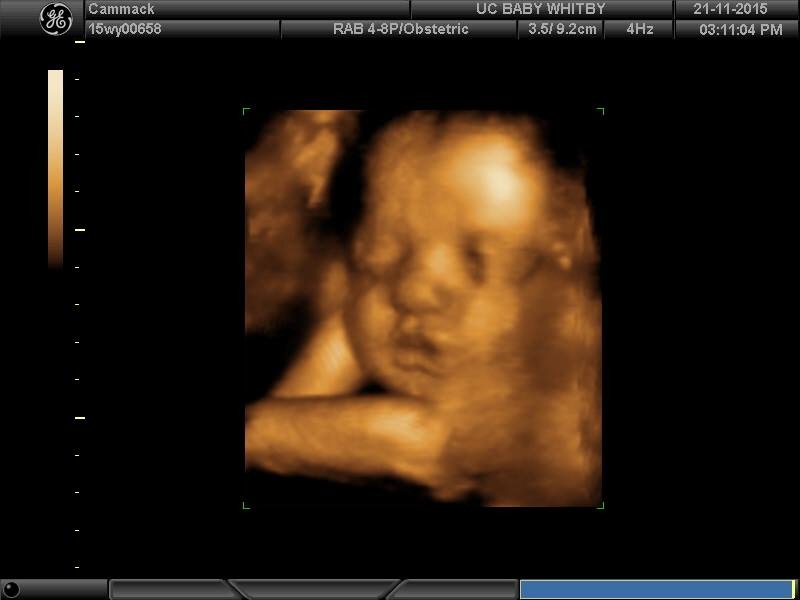

3rd Tri Ultrasound Sharing

Re: 3rd Tri Ultrasound Sharing